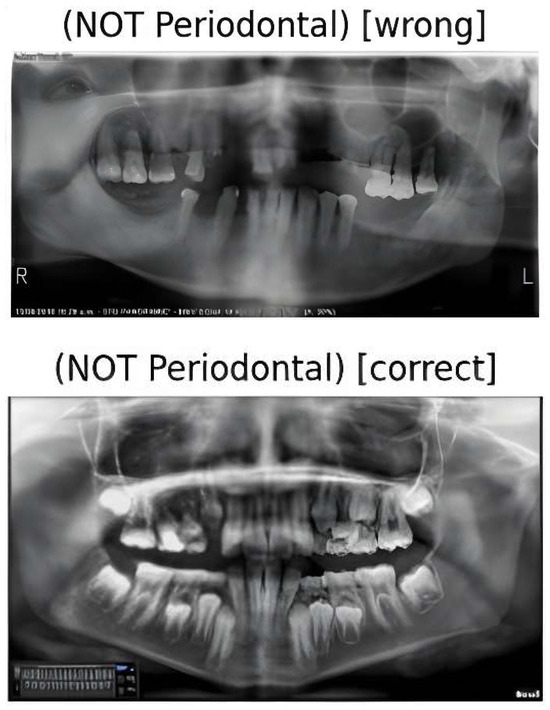

3.2. Results of the Primary Model (MobileNetV2)

4.2.1. The Primary Model (MobileNetV2)